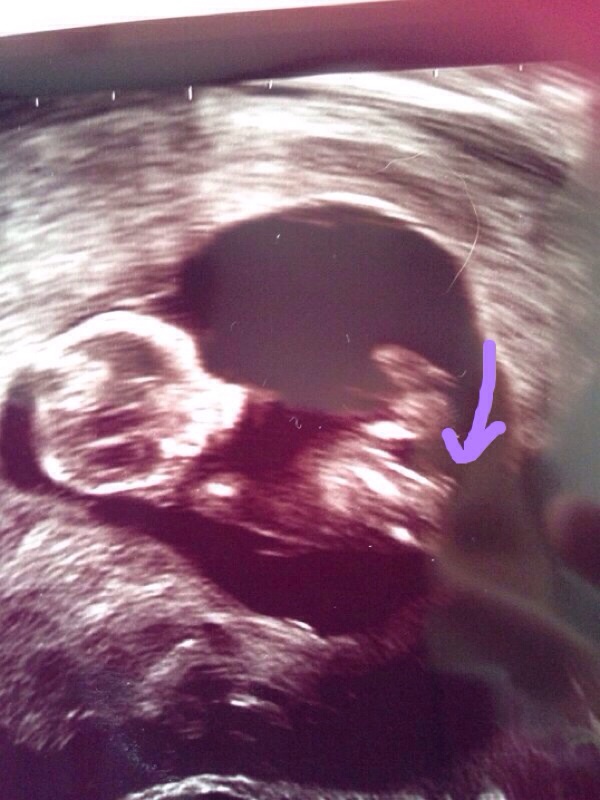

Other pics are of DD2!

It's another girl!!! JEEEEEEJJ!!!!

Confirmed at 15 weeks and 16 weeks and 18 weeks!